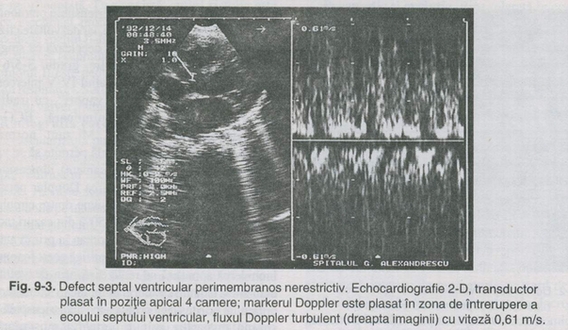

Echocardio grafia Doppler precizeaza gradientul sistolic, raportul dintre debitul circulatiei pulmonare si sistemice. Investigatiile invazive sunt rezervate cazurilor neclare si numai īn vederea precizarii detaliilor necesare corectiei chirurgicale. Angiografīa selectiva a ventriculului stāng permite localizarea exacta a defectului si posibile anomalii asociate.

evidentiaza dilatatia atriala si ventriculara stānga cu hiperkinezia ventriculului stāng legate de volumul suntului. Echocardiografia bidimensionala evidentiaza sediul, numarul, dimensiunea comunicarii inter-ventriculare, īn special īn proiectia patru camere.

ECG: niciodata normal, ramāne nec arac teri s tic pentru boala. De obicei axul QRS este deviat la stānga cu supraīncarcarea atriala si ventriculara stānga, uneori biventriculara. Echocardiografia īn modul M